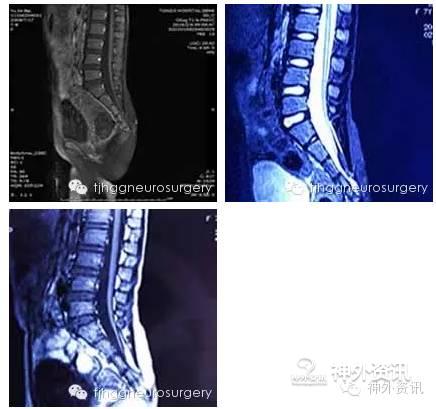

小喻同学今年七岁了,上学之前整天欢声笑语、活泼开朗,经常和小朋友一起玩耍、打闹。然而入学以来有了些许变化,不喜言笑,不愿主动与小朋友们接近了。家长一度怀疑是不是老师太严厉了,通过和班主任的交流回忆发现,小姑娘在学校尿过几次裤子,从那以后小孩子就变得畏手畏脑、胆胆怯怯的了。但是同学们也没有为此嘲笑她呀,老师还拿自家小孩的裤子给她换上了几次呢。原因在哪呢?老师仔细回忆发现每节课刚上课时还好,上了一会后,小姑娘就变得比较焦躁,无心听课了。小姑娘说自己要每节课都提前去厕所,不然就会尿裤子。老师和家长商量了后决定还是先到医院检查检查。

当地医院磁共振检查发现患儿先天性脊髓栓系,需要手术治疗。春节就在眼前了,一家三口跑了几家医院都建议春节假期过了再做,最后一家人抱着试一试的心态来我科咨询,雷霆教授仔细查看小孩后亦建议手术,家属反复向雷教授介绍家庭情况,恳请春节前期手术治疗。原来患儿一家住在大悟山区,父母常年在外打工,想趁着返乡时节,照顾女儿手术,以尽父母之责,陪伴女儿共度劫难。考虑到他们的实际困难,雷教授接受了他们的请求,并联系麻醉科、手术室团队给予协助,为了确保解除病痛而不带来意外伤害,特安排我科主院区电生理监测医师刘星、郭超前来支援。功夫不负有心人,术后三天患儿就恢复了自主排便功能。